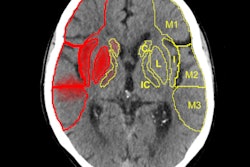

With color coding versus without, "there's a lot more information visible in the scan" showing asymmetry in perfusion between the left and right in an acute stroke patient, Meijs said of one example.

In the 3D volume rendering above, the reader can see a patient-specific color map, indicating the arrival time of blood to the brain. The color difference between the left and right hemisphere is caused by a vascular occlusion in the M1 segment. Due to collateral flow, the affected hemisphere is supplied with blood at a later arrival time, with orange and red hues indicating contrast arrival times several seconds later than green and blue. The green image below lacks color coding and took longer to interpret. Images courtesy of Midas Meijs.Overall, the average time to detection decreased from 37 seconds to 19.4 seconds (p < 0.03), and the average accuracy of vessel occlusion detection increased insignificantly from 0.825 to 0.85 with the use of color mapping. A single false-positive vessel occlusion was called by both observers using color mapping. However, both observers found the technique helpful and time-saving.